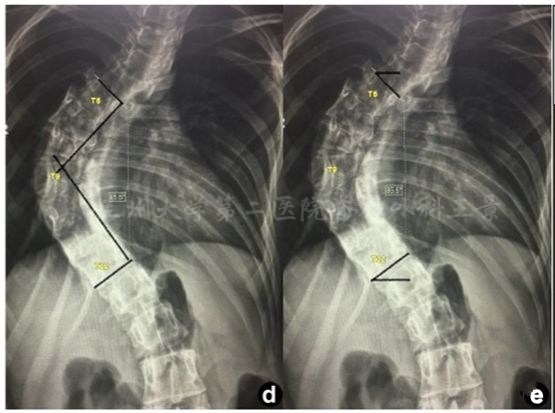

如法炮制,拍照测量脊柱侧弯Cobb角

为方便演示,照片标注上、下端椎终板连线

旋转照片使终板连线和网格线重叠

读出上、下端椎的倾角绝对值

相加后就是Cobb角

端椎倾角法快速测量Cobb角